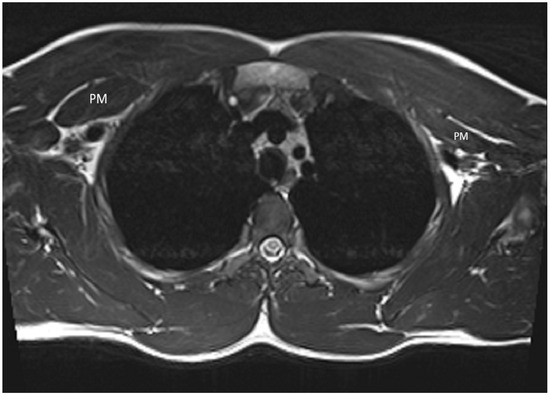

2. Case Presentation